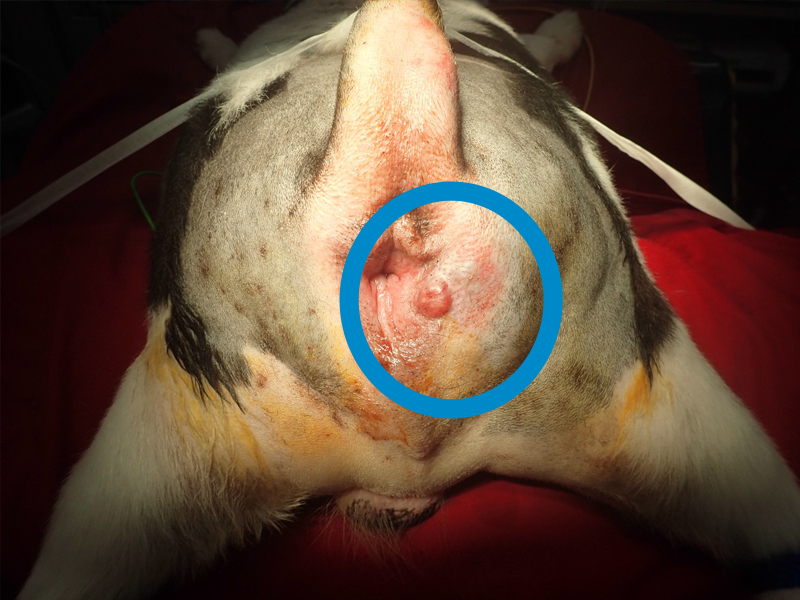

肛門嚢腺癌

肛門周りが腫れることがあります。

肛門腺の炎症、会陰ヘルニア、がんなどが原因です。

肛門嚢腺癌は、リンパ節転移を起こすことがあるので、レントゲン検査や超音波検査をしっかりと行います。

手術、放射線治療、抗がん剤、分子標的薬を組み合わせて治療を行います。